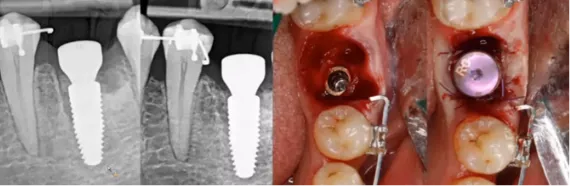

This case report shows the successful treatment of peri-implantitis using the GalvoSurge® Dental Implant Cleaning System combined with guided bone regeneration (GBR). A 66-year-old patient presented with peri-implantitis around implant #37, characterized by bleeding on probing, increased probing depths, and circumferential bone loss. Initial non-surgical interventions included prosthesis removal, installation of healing abutments, mechanical debridement, and antimicrobial irrigation. Subsequently, surgical treatment involved electrolytic cleaning with GalvoSurge®, application of a Straumann® Membrane Flex, and grafting with autogenous bone chips mixed with botiss maxgraft® granules. Over a two-year follow-up, the patient exhibited stable peri-implant conditions with no signs of inflammation or bone loss, underscoring the efficacy of this combined approach in managing peri-implantitis.

(With Dr. Viktorija Auzbikavičiūtė). The immediate placement of a Straumann® BLX implant in the posterior mandible of a 40-year-old patient is shown. The patient presented with secondary caries and subgingival destruction in tooth #36, rendering it non-restorable. Following atraumatic extraction and preservation of the interradicular septum, a 5.5 x 8 mm BLX implant was placed. The surgical site was augmented with allogenic bone graft (maxgraft®) and platelet-rich fibrin (PRF) to support healing. After four months, the implant demonstrated stable soft tissue integration, and a final zirconia ceramic crown was successfully installed, resulting in satisfactory functional and esthetic outcomes.

The strategies to enhance crestal bone stability following immediate implant placement in molar regions are explored and the complexities of achieving optimal outcomes in such procedures, particularly due to the anatomical challenges presented by molar extraction sites are explored. The importance of several key factors in ensuring successful implant integration and bone preservation is highlighted. These include performing atraumatic tooth extractions to minimize tissue damage, precise three-dimensional positioning of the implant to align with the patient's anatomy, and the use of individualized healing abutments tailored to the specific surgical site. Additionally, the role of implant design in influencing bone stability and the benefits of incorporating CAD/CAM technology and bone augmentation techniques to support the implant site is discussed. The webinar provides valuable insights into the complexities of immediate implant placement in molar areas and underscored the necessity of a comprehensive approach that considers surgical precision, prosthetic planning, and biological factors to achieve long-term success.​